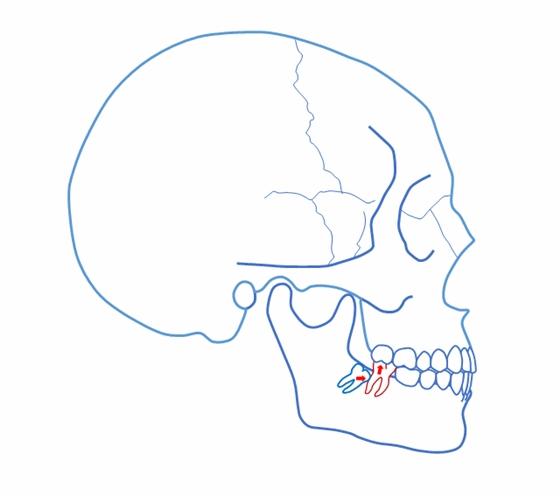

正位萌出到位,在牙尖交錯位建立咬合關系,只是一個靜態(tài)的狀況??陬M系統(tǒng)的功能要靠運動來實現(xiàn),而一旦動起來,很多“看”似建立了正常咬合關系的智齒很可能會造成咬合干擾,給整個口頜系統(tǒng)帶來傷害。

這樣 “萌出到位有咬合” 的智齒應該拔掉